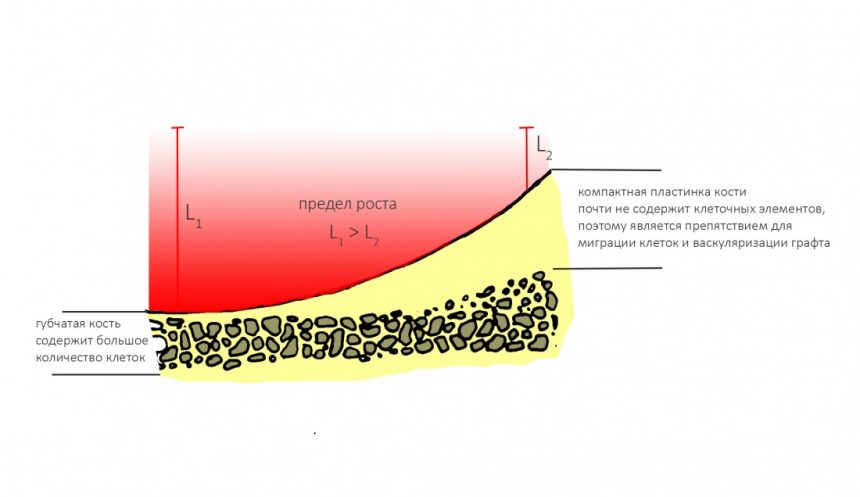

Вывод #1. У остеопластической операции с использованием чистых биоматериалов есть предел. Я называю его пределом роста. Он определяется скоростью и расстоянием миграции остеобластов и других клеток, участвующих в остеогенезе, ростом микрососудистого русла и т. д.:

Создание смешанного графта (т. е. введение в биоматериал аутокостной стружки) серьезно расширяет предел роста, но не преодолевает его. Причём, лишь небольшая (около 30%) аутокостной стружки участвует в регенерации, остальное «съедается» остеокластами и прочими макрофагами, при этом освобождаются т. н. «факторы роста» костной ткани — гормоноподобные вещества, инициирующие механизм остеогенеза:

Вывод #2. Чем больше площадь соприкосновения графта с костной тканью, тем больше миграции клеток, тем лучше он прорастает сосудами (васкуляризируется):

Напомню, что компактная пластинка костной ткани, особенно при биотипах D1 и D2, не почти не содержит способных к миграции остеобластов и, по сути, является препятствием для неё.